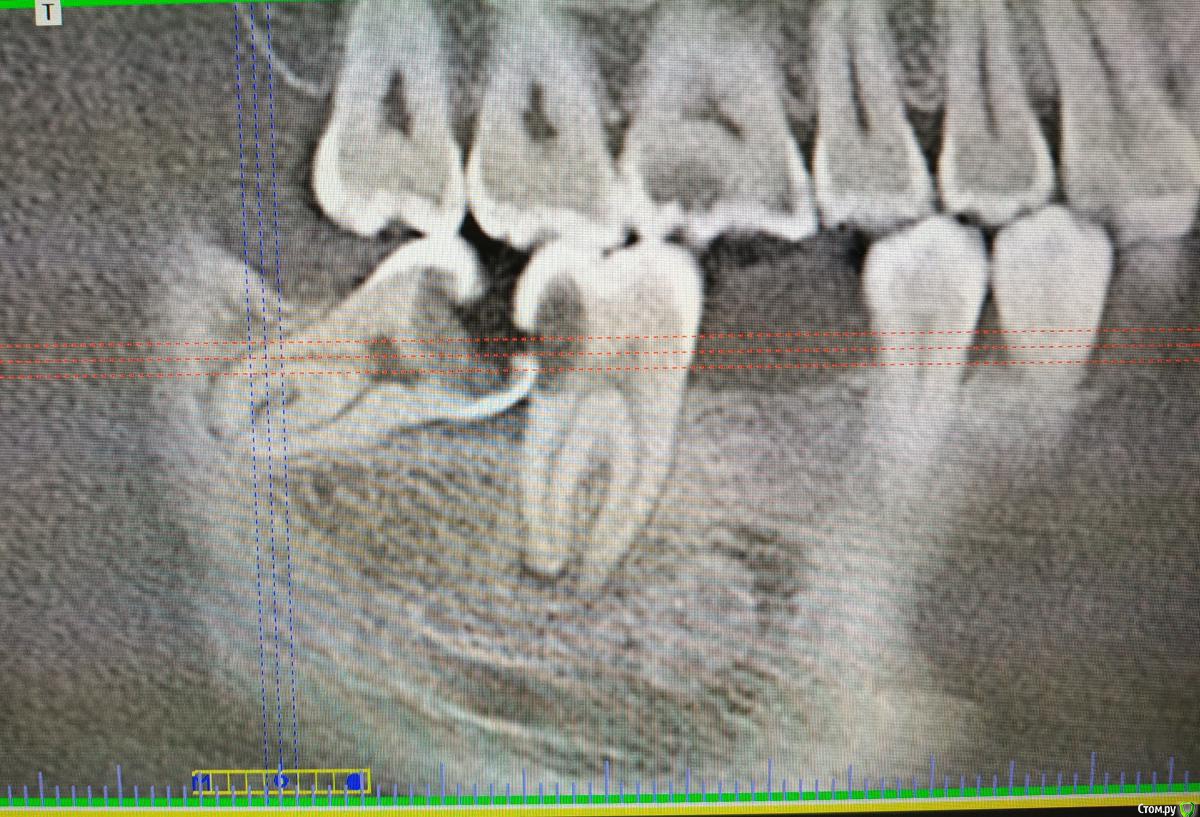

Den4558 Опубликовано 14 февраля, 2020 Поделиться Опубликовано 14 февраля, 2020 Доброго времени!Стоматолог изучив снимки не решился взяться за удаление зуба мудрости, посоветовав обратиться к коллегам с более богатым опытом в подобных случаях, что несколько меня насторожило и конечно возник вопрос насколько объективно все плохо.Сказал что очень вероятны плохие последствия после удаления, что придется обращаться в стационар.Помогите пожалуйста так ли это, насколько данная ситуация нетипична, и, если сохранять семерку (если вообще возможно) то насколько усложнена будет процедура по удалению восьмерки? Заранее благодарю. Ссылка на комментарий

It'sGeorgy Опубликовано 14 февраля, 2020 Поделиться Опубликовано 14 февраля, 2020 Доброго времени!Стоматолог изучив снимки не решился взяться за удаление зуба мудрости, посоветовав обратиться к коллегам с более богатым опытом в подобных случаях, что несколько меня насторожило и конечно возник вопрос насколько объективно все плохо.Сказал что очень вероятны плохие последствия после удаления, что придется обращаться в стационар.Здравствуйте. На предоставленных вами снимках не вижу ничего сложного/необычного. Риск осложнений после удаления немногим больше, чем после удаления любого другого зуба. Помогите пожалуйста так ли это, насколько данная ситуация нетипична, и, если сохранять семерку (если вообще возможно) то насколько усложнена будет процедура по удалению восьмерки? Сказать на 100% возможно ли сохранить семерку по одному снимку сложно, необходим очный осмотр после того, как полностью заживет рана от удаленного восьмого зуба. Но удалять прямо сейчас, вместе с восьмеркой, я бы точно не стал. 2 Ссылка на комментарий

Irouil Опубликовано 14 февраля, 2020 Поделиться Опубликовано 14 февраля, 2020 А в чем вопрос? Для доктора, который Вас смотрел, удаление сложное - он благоразумно, спасибо за это, предложил Вам найти специалиста с соответствующим опытом. Для более опытного специалиста оно будет рутинным. Такого и рекомендую Вам найти. Вопрос о сохранении 7-ки можно будет решать месяца через 3 после удаления 8-ки, но на этот период ее нужно будет пролечить и временно запломбировать. 4 Ссылка на комментарий

krokomot Опубликовано 16 февраля, 2020 Поделиться Опубликовано 16 февраля, 2020 Хорошо что есть такие доктора, которые в силах грамотно оценить свои возможности и направить к другому специалисту, не вовлекая, себя и пациента в ненужные риски. В удалении данного зуба для профессионального доктора, нет ничего сложного, бывает гораздо сложнее. Не забудьте вылечить 7й зуб, перед удалением обязательно. 4 Ссылка на комментарий